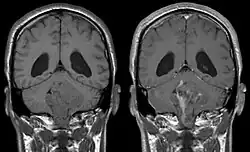

Na ressonância magnética, estes tumores apresentam um hipossinal em T1 , e são hiperintensas em T2; o realce pelo gadolínio é geralmente proeminente.[9] A extensão do tumor para o forame de Luska é comumente observado . A apresentação na tomografia computadorizada é muitas vezes como hiperdensidade com realce homogêneo. Cistos e calcificações são comuns. A presença de calcificação no interior de um tumor localizado no quarto ventrículo é altamente sugestiva de ependimoma.